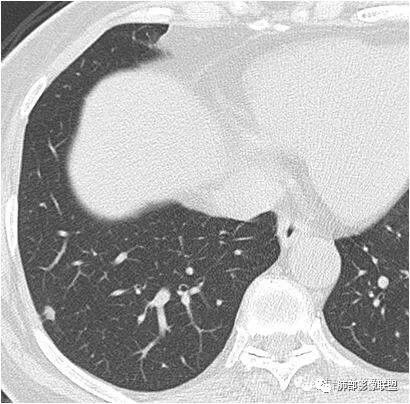

如图所示:

长径均小于12mm。典型的形状为三角形,也可以为梭形、圆形或椭圆形。诊断的关键在于见到1-5条细线与胸膜、叶间胸膜或静脉相连,有时状如坐落于电路板的“二极管”,但以薄层CT显示为佳。有作者病理对照线状影为小叶间隔,有作者病理对照为淋巴管。其实不矛盾,因为淋巴管走行于小叶间隔内。

诊断肺内淋巴结最关键指出在于薄层扫描见到细线状影与胸膜、叶间胸膜及肺静脉相连。